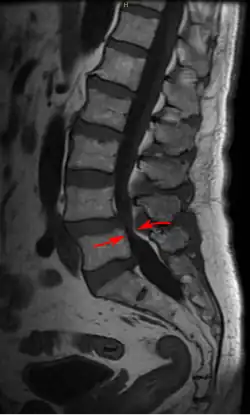

Lumbar vertebra showing central stenosis and lateral recess stenosis. | |

Spinal stenosis may be congenital (rarely) or acquired (degenerative), overlapping changes normally seen in the aging spine.[6][7] Stenosis can occur as either central stenosis (the narrowing of the entire canal) or foraminal stenosis (the narrowing of the foramen through which the nerve root exits the spinal canal). Severe narrowing of the lateral portion of the canal is called lateral recess stenosis. The ligamentum flavum (yellow ligament), an important structural component intimately adjacent to the posterior portion of the dural sac (nerve sac) can become thickened and cause stenosis. The articular facets, also in the posterior portion of the bony spine can become thickened and enlarged, causing stenosis. These changes are often called "trophic changes" or "facet trophism" in radiology reports. As the canal becomes smaller, resembling a triangular shape, it is called a "trefoil" canal.